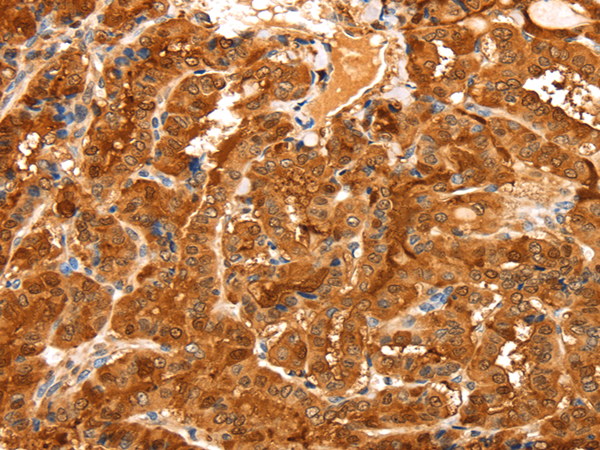

IHC positive control: |

Human thyroid cancer and Human brain |

IHC Recommend dilution: |

50-200 |